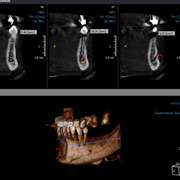

La radiología dental 3D ofrece al odontólogo informaciones muy detalladas para un diagnóstico más preciso y una mayor precisión en el tratamiento. La radiografía 3D le ofrece una visión más completa de la anatomía facial - prácticamente desde cualquier ángulo y perspectiva. Algo imposible de ver con imágenes 2D.

Visualiza la zona bucal, maxilar y dental desde una gran variedad de perspectivas

Puede ampliar cada área e incluso girarla

Nada permanece oculto: con la radiología dental obtendrá una imagen completa de la estructura oral, incluidos los huesos maxilares, estructuras blandas y nervios - todo ello con un único escaneado